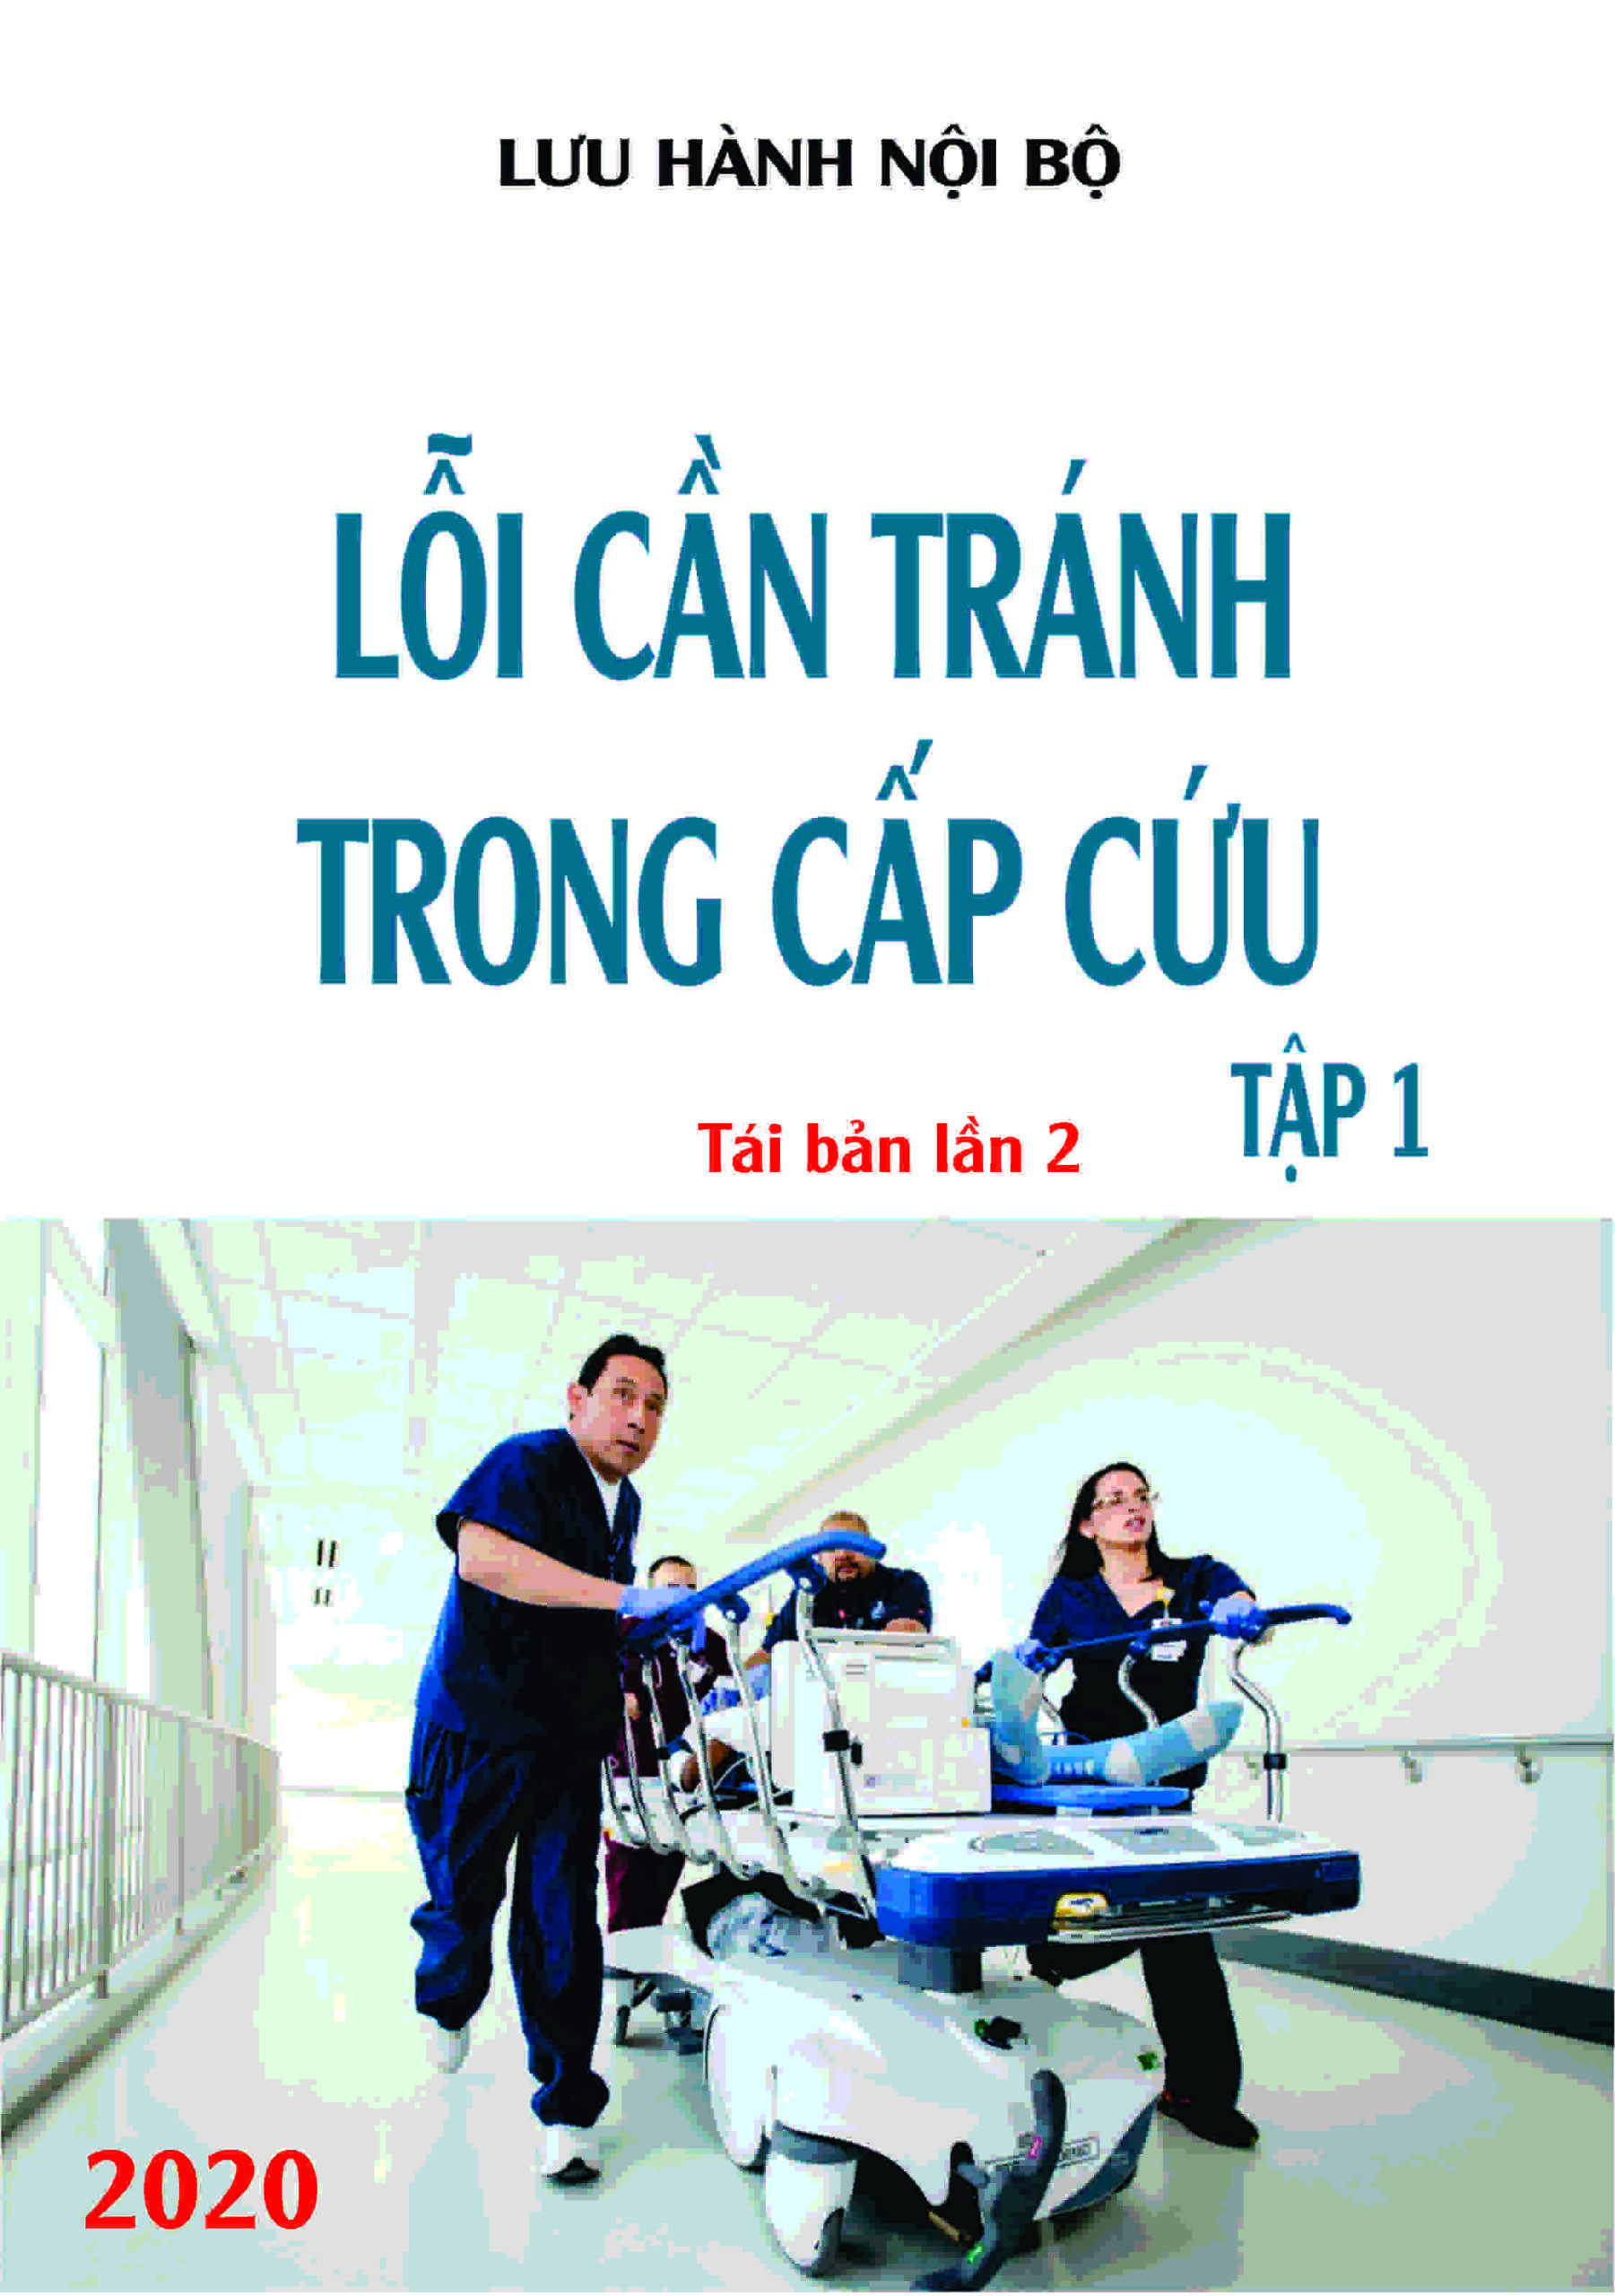

| Bảng 2. Các hình ảnh 2D tĩnh và động trong quy trình siêu âm tim | ||||||||

| Hình ảnh giải phẫu | Hình ảnh siêu âm | Ghi hình | Cấu trúc cần khảo sát | |||||

| 2.1. Mặt cắt trục dài cạnh ức với depth sâu

|

||||||||

|

|

Cửa sổ siêu âm cạnh ức

Mặt cắt trục dài cạnh ức Đầu dò đặt tại bờ trái xương ức với marker hướng lên vai phải của bệnh nhân. |

Khoang màng ngoài tim Khoang màng phổi | |||||

| 2.2. Mặt cắt trục dài cạnh ức khu trú vào thất trái

|

||||||||

|

|

Cửa sổ siêu âm cạnh ức

Mặt cắt trục dài cạnh ức Đầu dò đặt tại bờ trái xương ức với marker hướng lên vai phải của bệnh nhân. Chùm siêu âm đặt vuông góc với thất trái. |

Nhĩ trái (LA)

Van hai lá (MV) Thất trái (LV) Đường ra thất trái (LVOT) Van động mạch chủ (AV) Vách liên thất (IVS) Thất phải (RV) |

|||||

| 2.3. Mặt cắt trục dài cạnh ức phóng đại van động mạch chủ

|

||||||||

|

|

Cửa sổ siêu âm cạnh ức

Mặt cắt trục dài cạnh ức Đặt hộp phóng đại vào vị trí van động mạch chủ, đường ra thất trái, động mạch chủ lên Chùm siêu âm đặt vuông góc với cấu trúc và có thể đặt đầu dò lên các khoang liên sườn cao hơn nếu cần. |

Van động mạch chủ (AV) | |||||

| 2.4. Mặt cắt trục dài cạnh ức phóng đại van hai lá |

||||||||

|

|

Cửa sổ siêu âm cạnh ức

Mặt cắt trục dài cạnh ức Đặt hộp phóng đại vào vị trí van hai lá Ghi được toàn bộ chuyển động của hai lá van, đoạn gần của dây chằng và vòng van. |

Van hai lá (MV)

Nhĩ trái (LA) |

|||||

| 2.5. Mặt cắt trục dài cạnh ức qua đường ra thất phải |

||||||||

|

|

Cửa sổ siêu âm cạnh ức

Mặt cắt trục dài cạnh ức Ngửa và xoay đầu dò về phía đường ra thất phải/ |

Đường ra thất phải (RVOT) Van động mạch phổi (PV) Động mạch phổi (PA) |

|||||

| 2.6. Mặt cắt trục dài cạnh ức qua buồng nhận thất phải |

||||||||

|

|

Cửa sổ siêu âm cạnh ức

Mặt cắt trục dài cạnh ức Ngả đầu dò xuống dưới hướng về phía đùi phải của bệnh nhân |

Nhĩ phải (RA) Van ba lá (TV) Thất phải (RV) |

|||||